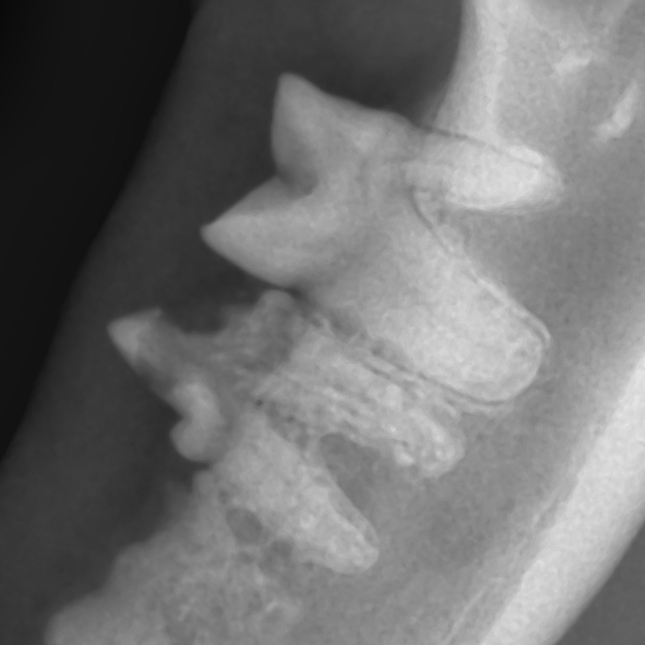

口腔内X線検査を行うと、一部の歯が溶けています。複数の歯で溶解が認められましたがそのうちの一か所を載せています。(

)。

写真の2本の歯のうち、左側の歯はレントゲン写真を見ても明らかに密度が薄く溶けたような様子をしています。これは、破歯細胞という「歯を壊す働きを持つ細胞」が、何らかの原因で歯の組織を吸収してしまうことで生じる歯の吸収病巣という疾患です。